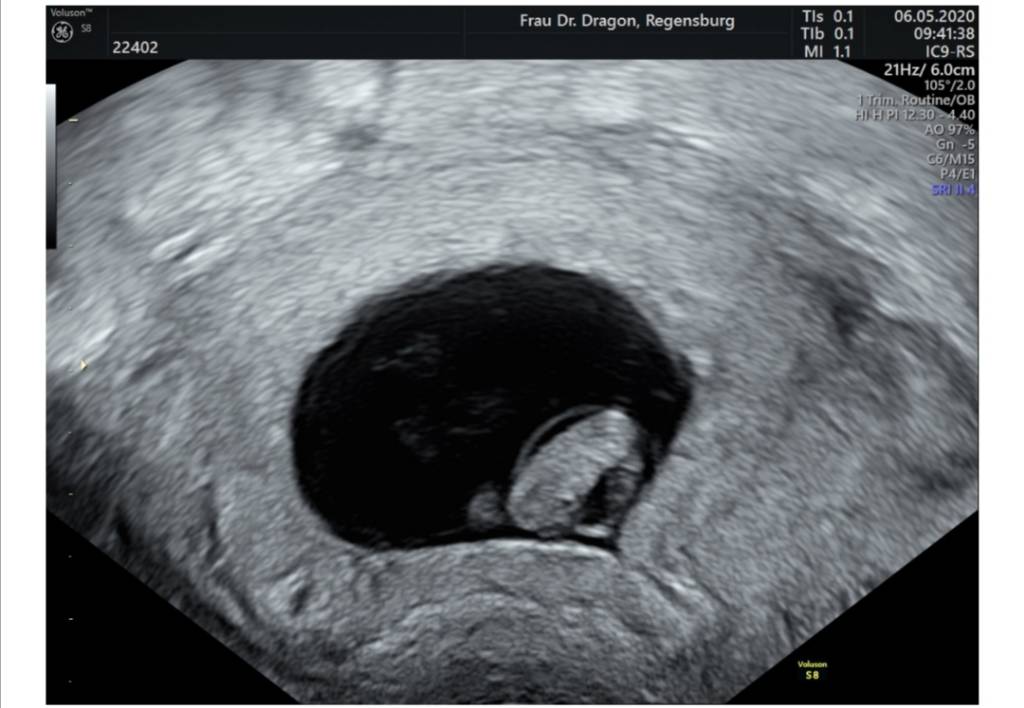

Miałam dodać jak u mnie wyglądają te bliźniaki. To jest 7+3. Mierzone było tylko to pierwsze, bo drugie siedzi za nim i widać tylko bokiem na usg